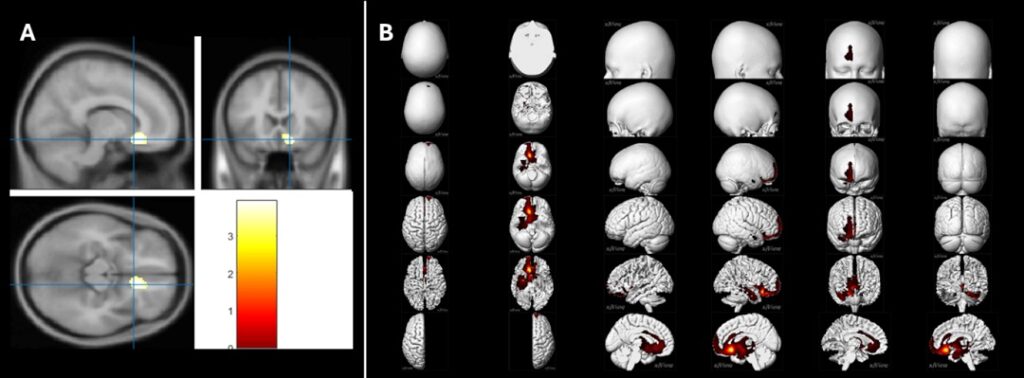

Les jours où ces émotions négatives étaient collectivement les plus intenses, les chercheurs ont observé une baisse significative du métabolisme cérébral dans le cortex préfrontal ventromédian (vmPFC) et le cortex cingulaire antérieur (ACC), deux régions centrales du réseau cérébral de la peur, connues pour leur rôle dans la gestion des émotions et du stress.